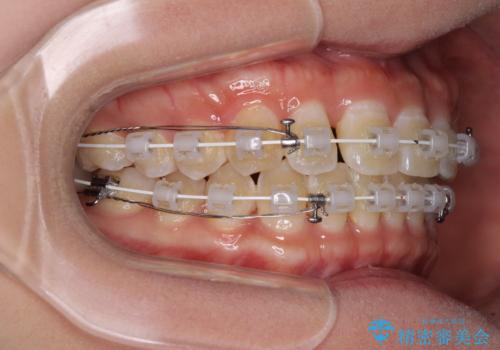

- 矯正装置

- 審美装置

正中がなかなか合わずに、2年近くの治療期間を要しました。